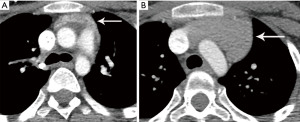

Thymoma typically presents as a smooth or lobular mass involving one lobe of the thymus, although bilateral involvement can occur (39). Most thymomas demonstrate homogeneous enhancement, although, approximately one third can be heterogeneous due to areas of hemorrhage, necrosis, cystic change, or calcification (1) (Figures 8,9). Imaging characteristics can vary according to WHO histological classification, with vascular invasion and pleural/pericardial involvement more common with more aggressive histology (Figure 2). The thymomas with the more aggressive histologies tend to be larger, more lobular or irregular, have cystic or necrotic change, areas of calcification, or evidence of infiltration into surrounding fat (40-42) (Figure 10).

The role of FDG PET/CT in thymoma imaging is limited. Given the presence of FDG uptake in the normal and hyperplastic thymus, especially in younger adults and children, false-positive results can occur. In fact, physiologic uptake has been reported in 28% of patients under 40 years of age and up to 73% in children less than 13 years of age (44). PET/CT has not been shown to differentiate different WHO histological classifications of thymic tumors, although the more aggressive histologies tend towards higher FDG uptake (45,46) (Figures 2,3). Indium111 octreotide nuclear medicine scans have now been replaced by 68Ga-labeled somatostatin analogues because 68Ga-labeled somatostatin analogues, such as 68Ga-DOTATATE, are used for PET/CT, and thus provide better resolution.

Thymic carcinoma and thymic neuroendocrine tumors have similar imaging characteristics which may often overlap with the more aggressive histologies of thymoma, such as B3 thymoma. Thymic carcinomas and neuroendocrine tumors commonly present as large prevascular masses with irregular or poorly marginated borders, areas of necrosis or cystic change, and hemorrhage. Compared with thymomas, there is a greater incidence of local invasion (1) (Figures 2,11). Pleural or pericardial nodules, pleural effusion, and distant metastasis are more commonly seen with thymic carcinoma or thymic neuroendocrine tumor than thymoma (Figure 12). More aggressive thymic epithelial tumors can invade or compress the SVC resulting in SVC syndrome. This is a clinical syndrome marked by swelling of the neck, face, and upper extremities, with associated cough, headache, and shortness of breath. Pleural metastatic disease, which is more common in thymic carcinoma and thymic neuroendocrine carcinoma, generally consists of small enhancing pleural nodules or areas of enhancing pleural thickening. These are generally adequately assessed with thin-slice contrast-enhanced CT, although, contrast-enhanced MRI and PET/CT can be of additional benefit in questionable cases.

As noted, FDG PET/CT does not reliably differentiate between the different histological types of thymoma. Several small studies, however, have suggested that FDG PET/CT can help differentiate thymoma from thymic carcinoma using various cutoffs of SUV max ranging between 4.6 and 6.3 (49,50). Since the more aggressive tumor histologies are FDG avid, FDG PET/CT can be useful in the assessment and follow-up of thymic carcinoma but is not routinely recommended (51). Thymic neuroendocrine tumors can additionally be evaluated with 68Ga-DOTATATE PET/CT which may demonstrate improved sensitivity for lesion detection compared with FDG PET/CT which can help identify tumors that are candidates for peptide receptor radiotherapy (PRRT) with 177Lutetium (51).